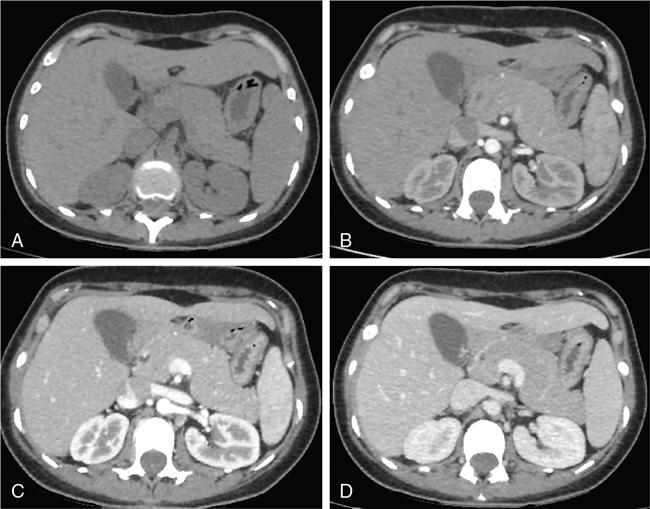

Ritu K. Kashikar, Shrinivas B. Desai, Pooja Punjani Vyas, Nilesh Doctor, Vivek Shetty Advancement and extensive use of imaging in recent times has to lead to increased detection and recognition of cystic pancreatic masses. Imaging however, plays a vital role in noninvasive diagnosis of these lesions, avoiding unnecessary intervention and planning management and follow up guidelines. The aetiology of pancreatic cysts ranges from primary cystic neoplasm to cystic degeneration of solid neoplasm to nonneoplastic cysts (Table 9.19.1). Cystic tumours of the pancreas comprise around 10%–15% of cystic lesions of the pancreas. The aim of this chapter is to educate the reader regarding imaging features of cystic lesions of pancreas, how to differentiate between cysts which can be left alone and those that require further management and also emphasize on latest international guidelines used in stratification of these lesions. Cystic pancreatic lesions are often incidentally detected on USG abdomen performed for other reasons. Although USG is an excellent modality for evaluation of cystic lesions elsewhere, it is unable to adequately characterize pancreatic cysts due to retroperitoneal location of the organ and other confounding factors such as obesity and gases. Most lesions detected on USG require characterization with either MDCT or MRI with MRCP. CEUS improves accuracy in the differentiation between a solid and a cystic lesion and also in determining whether enhancing septa or nodules are present within the cystic lesion. Currently USG also does not have a role in follow up algorithms of pancreatic cystic lesions. Multidetector CT evaluation of pancreatic lesions is best performed with a multiphasic technique (Table 9.19.2). The phases include a precontrast scan, an early arterial angiographic phase, a pancreatic parenchymal phase, and a portal venous phase. The precontrast scan is important for detection of calcification, which may be diagnostic of some lesions. Mucinous cystic neoplasms may be hyperdense on nonenhanced scan suggesting mucin content or haemorrhage. The arterial phase aids in detection of hyperenhancement neovascularity and arterial involvement in pancreatic masses. Optimal parenchymal enhancement of the pancreas is achieved at 35–45 seconds after initiation of injection of contrast agent. This is the pancreatic parenchymal phase. It is in this phase that the tumour pancreas contrast is maximum (Fig. 9.19.1, Table 9.19.3). Most hypoenhancing pancreatic lesions are best detected in this phase. The portal venous phase allows in detection of venous involvement and hepatic metastasis. Delayed phase is typically not required in cystic masses. MDCT has an accuracy of 56%–85% for characterization of cystic pancreatic lesions. MR imaging affords the best noninvasive means for the evaluation of cystic lesions of the pancreas due to superior soft tissue resolution. The helpful distinguishing characteristics of cystic pancreatic lesions, morphology of septae, relation to pancreatic duct are easier to detect at MR imaging and MR cholangiopancreatography (MRCP) than at CT (Table 9.19.4). Studies however indicate that MDCT and MRI are comparable in identifying malignant behaviour of cystic pancreatic lesions. The MRI protocol for evaluation of cystic lesions of pancreas includes T2-weighted single-shot fast spin-echo, T1-weighted in-phase and opposed-phase gradient echo, diffusion-weighted imaging, T2-weighted fat-suppressed fast spin-echo. Three-dimensional T1-weighted fat-suppressed spoiled gradient-echo T2-weighted MRCP. Postcontrast protocol includes dynamic three-dimensional T1-weighted fat-suppressed spoiled gradient-echo (in arterial, pancreatic and portal venous phases) (Fig. 9.19.2, Table 9.19.3). DWI has not found much utility in cystic neoplasms owing to overlap in ADC values. Some studies suggest role in distinguishing malignant from benign tumours in the case of mucinous cystadenoma and IPMN. Secretin is a peptide hormone produced in the intestinal mucosa, which stimulates the secretion of bicarbonate-rich fluid into the pancreatic ducts and transiently increases the tone of the sphincter of Oddi. The increased fluid distention of the pancreatic duct allows better study of ductal anatomy and identifying communication of pancreatic cystic lesions with the pancreatic duct. EUS is excellent in characterization of cystic lesions of pancreas. The proximity between the transducer and the lesions allows precise definition of the structural component of the cysts and components such as small mural nodules are better visualized with EUS than with other modalities. The other advantage of EUS is that cysts fluid aspiration and cytology can be performed. Tumour markers, genetic markers can be evaluated in the aspirated fluid. This allows comprehensive evaluation of cystic lesion. EUS also has therapeutic advantages allowing endoscopic draining of pseudocysts. Recently endoscopic ablation of cysts has been performed. These advantages have led to increasing use of EUS in recent years. This modality is however not indicated in all lesions and imaging should be able to stratify lesions requiring further invasive investigations. Studies have found PET CT comparable to PET alone or CT to determine presence of malignancy in cystic lesions. False positive findings may however be problematic. There is however no consensus for routinely using PET CT in characterization of cystic pancreatic masses. Serum CA19-9 and CEA are routinely done in all pancreatic masses. Though role in cystic lesions is still controversial. Serous cystadenoma is a benign neoplasm composed of glycogen-rich epithelial cells that form innumerable small thin-walled cysts containing serous fluid. It is the prototype microcystic pancreatic neoplasm. They occur frequently in older women (median age, 65 years) and is also called as grandmother lesion. Approximately 40% of pancreatic serous cystadenoma arise from the pancreatic head and uncinate process and 60% arise from the pancreatic body and tail. Serous cystadenomas are usually discovered incidentally at imaging; however, those that are large may cause symptoms. Patients may present with abdominal pain, palpable mass, anorexia, fatigue/malaise, or weight loss. Rarely the patient may present with jaundice. Genetic alterations similar to those in VHL are seen in sporadic SCA and include tumour suppressor gene VHL mutations and overexpression of vascular endothelial growth factor (VEGF). Allelic loss in chromosome 3 have seen in up to 40% cases of sporadic SCA. Serous cystadenomas are variable in size. The size ranges from <0.1 to 25 cm. The tumours are grossly well demarcated from the surrounding parenchyma. The gross appearance of the lesions is variable. It could be microcystic, consisting of innumerable small cysts giving the macroscopic appearance of a sponge or honeycomb. The presence of multiple, microscopic SCN is characteristic of von Hippel–Lindau (VHL). This variety show a centrally located area of fibrotic scar. In Macrocystic/oligocystic variant, borders with the surrounding parenchyma are less defined and the cystic lesion generally does not exhibit a central scar. The Solid variant, the lack of cystic spaces on gross inspection often gives the initial impression of a neuroendocrine or solid pseudopapillary neoplasm. Serous cystadenomas show nonviscous, clear-to-yellow cyst fluid, which provides an important clue to the distinction of SN from mucinous neoplasms. In contrast to intraductal papillary mucinous neoplasm, there is no connection with main or branch pancreatic ducts. These are clinically benign pancreatic epithelial neoplasms exhibiting serous morphology, characterized by a monotonous, cuboidal epithelial cell proliferation with marked cytoplasmic clearing due to intracellular glycogen. The centrally located epithelial cell nuclei are uniformly round to ovoid and not particularly large or hyperchromatic. Abundant diastase-sensitive cytoplasmic glycogen is highlighted by a periodic acid–Schiff stain. These lesions do not show evidence of necrosis, infiltrative architecture, or lymphovascular/perineural invasion, and mitotic figures are generally not observed. A variably prominent pseudocapsule of fibrosis divides parenchyma from the neoplasm On USG the microcystic variant shows lobulated contour with multiple tiny anechoic cysts separated by septae. the central scar containing calcification can be seen if present. Extremely microcystic, honeycomb variant may resemble a solid lesion at conventional US. The macrocystic type, can be mixed type with multiple large (>20 mm) and small cysts, and the unilocular type, which is more difficult to differentiate from mucinous cystadenoma (MCA). Enhancement of the intralesional sepatations is seen on contrast-enhanced USG allowing better characterization of the lesion. The central scar can show homogenous enhancement. Honeycomb variety appears as a hypervascular lesion owing to its extremely microcystic morphology and may resemble solid masses like neuroendocrine tumours. Pancreatic serous cystadenoma can have a varied appearance on CT depending on the morphologic patterns. Serous cystadenomas are typically solitary but may be multiple in von Hippel–Lindau disease, causing an appearance of disseminated involvement (Table 9.19.5). As mentioned previously, the polycystic pattern is the most common appearance of serous cystadenoma. A pattern of a bosselated collection of cysts that usually number more than six is seen. Each cyst may range from a few millimetres to 2 cm in size (Fig. 9.19.5). The other classic CT features include a lobulated contour and presence of a central stellate scar with calcification. This scar is seen in 30% cases and when present is strongly suggestive of the diagnosis. The intralesional fibrous septae show early enhancement after contrast administration. This is a distinguishing feature, as serous cystadenoma is the only hypervascular lesion among the cystic pancreatic neoplasms. Tiny cysts mimicking a honeycomb are the hallmark of this variant and may be poorly depicted as individual cysts on CT. On unenhanced CT, the honeycomb pattern may appear as a well-marginated lesion with soft tissue or mixed attenuation, depending on the size of the cysts and the amount of fibrous tissue. Moderate to strong enhancement is seen in these lesions (Fig. 9.19.6). This appears as a unilocular cyst or it may contain fewer large (>2 cm) cysts. Imaging Features include a lobulated contour, lack of a prominent thickened peripheral wall, and location in the head of the pancreas (Fig. 9.19.7). Owing to its supreme soft tissue resolution, MRI is the modality of choice in diagnosis of serous cystadenomas. The classic MRI features of microcystic variant includes a lobulated lesion with multiple small T2 hyperintense and T1 hypointense cysts with intervening hypointense fibrous sepate. These lesions do not communicate with the pancreatic duct; hence no dilatation is usually seen. Dilatation of pancreatic duct has however been reported in larger lesions. After the administration of gadolinium, the hypervascularization of the central scar and of internal septa may be seen. The morphology of the honeycomb pattern may also be better depicted on MRI. Multiple tiny T2 hyperintense cysts with intervening hypointense septae are seen (Fig. 9.19.8). The oligocystic variant shows fewer larger T2 hyperintense and T1 hypointense cysts and can mimic mucinous cystadenoma. However, the lobulated contour, together with the absence of wall enhancement and a wall thickness less than 2 mm, suggest the correct diagnosis (Fig. 9.19.9) (Table 9.19.6). The differential diagnosis of serous cystadenoma depends on the variety and are listed in Tables 9.19.7 and 9.19.8. Lesions with classic imaging features do not require further investigation or fluid analysis. The fluid in classic cystadenomas is yellow in colour and does not show elevated amylase, mucin or tumour markers. Approximately 20%–50% cases show cytological positivity for periodic acid-Schiff and cytokeratin AE1 and 3. Hemosiderin laden macrophages also do not have high diagnostic accuracy and are seen in only about 43% cases. Current management guidelines suggest (Table 9.19.9). Resection involves distal pancreatectomy or Whipples, depending on location of the tumours and is currently reserved for truly symptomatic cases. Mucinous cystic tumours are a rare subset of cystic neoplasms, constituting approximately 2.5% of pancreatic exocrine tumours. TABLE 9.19.10 The defining and characteristic histopathologic feature of mucinous cystic neoplasms (MCNs) is the presence of ovarian-type stroma similar to that observed in biliary cystadenomas. International Association of Pancreatology recommend that all suspected MCNs be surgically resected. A significant female predilection is seen with approximately 99.7% cases seen in women. As opposed to serous cystadenomas these lesions occur in middle aged women and hence the term mother lesions is used to describe these. The approximate age of occurrence is 50 years with a range from 20–82 years. Mucinous cystic tumours are a dominant cyst that is round or oval and is encapsulated. MCNs may grow slowly over time, at an average rate of 4 mm per year. The most common locations are the pancreatic body and tail (up to 75%). Stromal elements similar to ovarian stroma are the hallmark and key feature that aids in differentiation from IPMN, whose stromal elements are ductal in origin. Tall columnar cells with intracellular mucin arranged in a single row or vertically, forming papillary or polypoidal projections, constitute the epithelial elements. Portions of benign appearing epithelium can be seen adjacent to areas of invasive carcinoma in the same tumour. These lesions show smooth contour on gross appearance with few internal sepate. Peripheral calcification, mural nodule if present suggest malignant cyst (Fig. 9.19.11, Table 9.19.11). Lesions may be asymptomatic in 25% cases. Patients my present with pain in abdomen. Mucinous cystadenoma can also present with pancreatitis. Considering most lesions are located in distal body and tail involvement of splenic vein may lead to left sided portal hypertension. Mucinous cystic tumour is a well-circumscribed cystic mass in the pancreas. Lesions can have an irregular contour to the wall, septations, mural nodularity, and peripheral calcifications. The lesion may however be echogenic due to high by mucin content or haemorrhage which may impair the detection of other features. CEUS may improve detection rate of septa and mural nodules. Lesions are typically well-circumscribed with smooth contour. On unenhanced CT, mucinous cystadenoma may appear hypodense or slightly hyperdense content, due to the presence of variable amount of mucin and haemorrhage. Curvilinear calcifications occur along the periphery of the lesion and are seen in 15% of cases, in contrast study enhancement of the fibrous cyst wall along with enhancement of any septations or mural nodules is seen (Figs. 9.19.12 and 9.19.13).